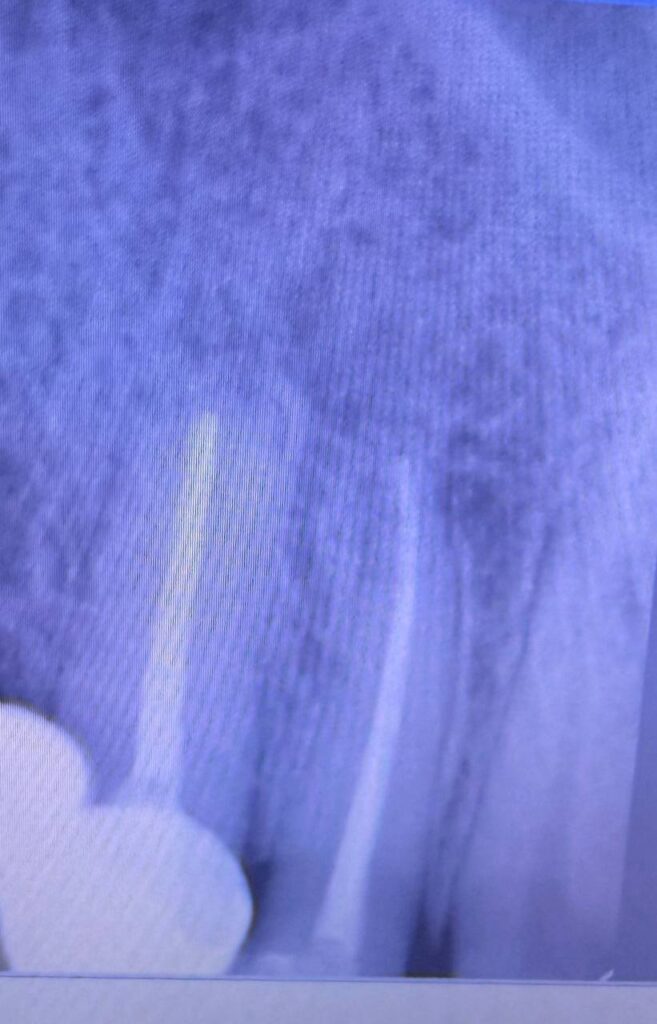

☑️ наявність кісти або гранульоми на верхівці кореня

☑️ злам інструменту в каналі зуба